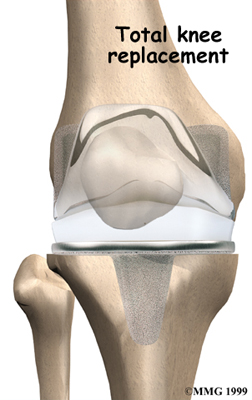

Artificial Knee Replacement

An artificial knee replacement is the ultimate solution for advanced knee OA.

Surgeons prefer not to put a new knee joint in patients younger than 60. This is because younger patients are generally more active and might put too much stress on the joint, causing it to loosen or even crack. A revision surgery to replace a damaged prosthesis is harder to do, has more possible complications, and is usually less successful than a first-time joint replacement surgery.

Related Document: FYZICAL North Port's Guide to Artificial Joint Replacement of the Knee